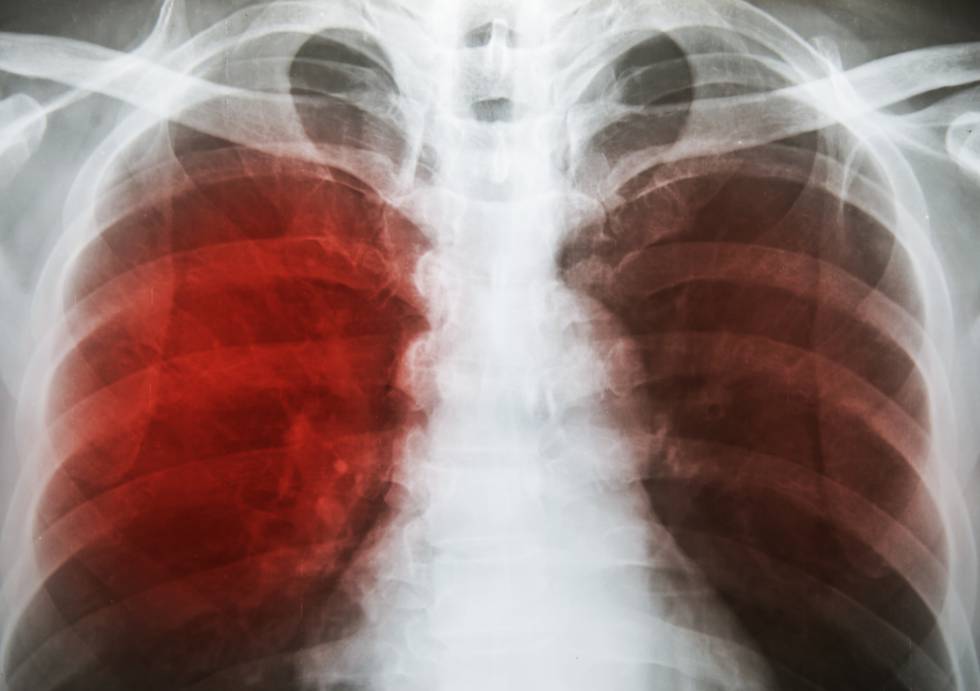

Los pacientes enfermos con TB se han visto afectados con la llegada de la pandemia. El COVID-19 puede afectar a las personas infectadas o enfermas con TB, antes, durante o una vez curadas, facilitando en algunos casos el paso de infección latente a la enfermedad por una alteración del sistema inmunológico. También ha aumentado la posibilidad de hacer más severa la evolución de la TB por la mayor extensión de las lesiones pulmonares.

La coexistencia de Tuberculosis-COVID-19 se presenta en nuestro país con un número aún no determinado, pero con un riesgo que suponemos aumentado debido a las lesiones pulmonares preexistentes en el pulmón y al estado de depresión inmunológica que presentan algunos de los pacientes, sumado al estrés que presenta esta pandemia del COVID-19.